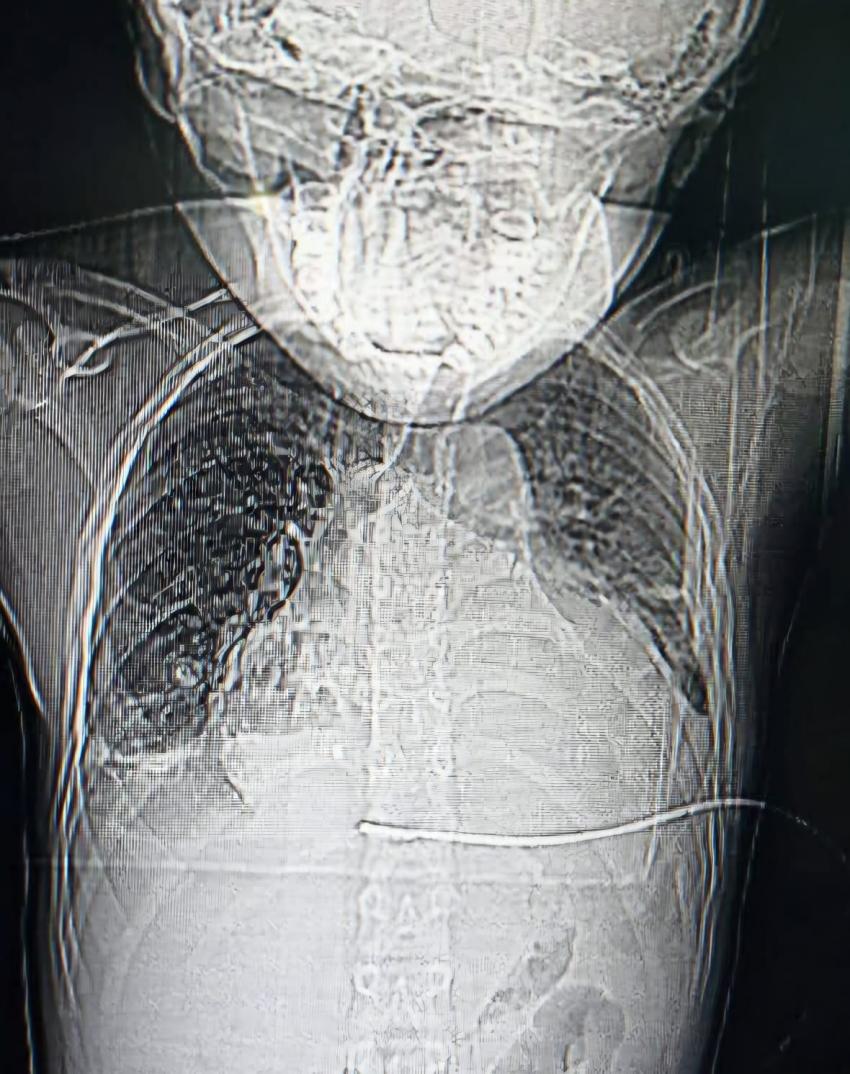

سرايا - تمكن فريق طبي متخصص بمستشفى الأميرة بسمة التعليمي، وبإشراف أخصائي الأشعة التداخلية وقسطرة الأوعية الدموية الدكتور محمد نزال، من إنقاذ حياة طفل يبلغ من العمر 13 عامًا بعملية نادرة ودقيقة، حيث كان يعاني الطفل من حالة طبية تسمى "إنصباب التامور" (Pericardial Effusion).

وقال مدير مستشفى الأميرة بسمة الدكتور ابراهيم شهابات، اليوم السبت، إن هذه الحالة الطبية تسمى "إنصباب التامور"، وهو تجمع سوائل حول القلب داخل غشاء التامور، ما أدى إلى تطور الحالة نحو "انضغاط القلب"، وهي حالة طارئة تستدعي التدخل العاجل فوراً خلال ساعات قليلة للحفاظ على حياة المريض.

وأضاف أنه جرى وضع أنبوب تصريف باستخدام تقنيات متقدمة وتوجيه إشعاعي دقيق للحالة، ما مكّن من إزالة السوائل من القلب، واستعادة العلامات الحيوية للمريض خلال دقائق معدودة، حيث زال الخطر عنه واصبحت حالته الصحية جيدة جدا.